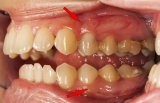

With prolonged conflict activity a flat growth (absorptive type) develops in the submucosa of the mouth. In the palate, salivary glands, tonsils, pharynx, and throat it can also take a cauliflower-shaped form (secretory type). If the papillae of the tongue that contain the taste buds are affected, the additional cells provide an enhanced sense of taste in order to be able to analyze (see sensory quality) the “morsel” (compare with hypersensitivity to taste related to the posterior third of the tongue).

A large growth is usually diagnosed as an oral cancer (compare with “oral cancer” related to the mouth surface mucosa) or as a “glandular tumor” if it involves the salivary glands.

In the mouth, the healing phase presents as canker sores (aphthous ulcers) on the inside of the lips or cheeks, on the palate or tongue, or in all areas of the mouth, depending on the perception of the conflict situation (compare with aphthous ulcers related to the mouth surface mucosa). Canker sores appear as round or oval white spots with an inflamed border. They can be quite painful. On the gums, the pus-filled pocket is called a “dental abscess” or gum abscess. The tuberculous discharge causes bad breath.

If the required microbes are not available upon the resolution of the conflict, the additional cells remain. Eventually, the growth becomes encapsulated with connective tissue. In conventional medicine, this is usually diagnosed as a mouth polyp or “benign cancer”. A gum polyp might reach into the neck of a tooth.